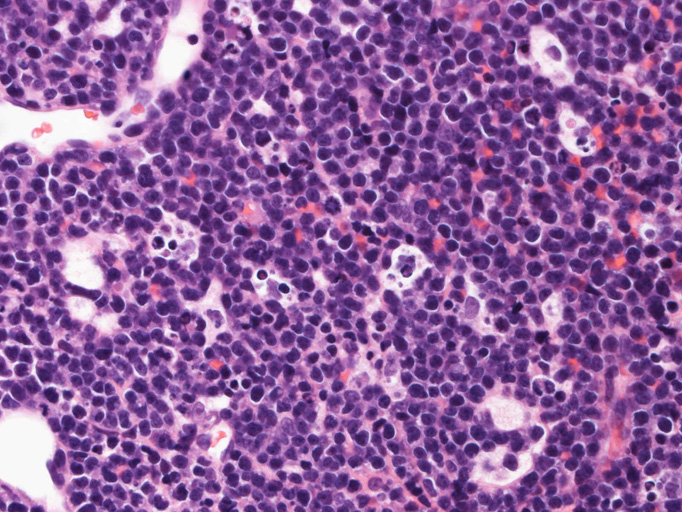

Burkitt lymphoma

72歳 男性

腹部膨満感で他院を受診. 黄疸と心窩部腫瘤を触れCTでは管内胆管の拡張と左葉の腫瘤を認めた。精査治療のため当院消化器内科を紹介される。 ENBD留置などの処置で減黄を行う。ERCPによる胆汁細胞診では少数のatypical lymphcytesを認めるが確診できず。肝生検をおこなった。

エコーガイド下肝腫瘤針生検組織

尾状葉の腫瘍から16G, 11mm穿刺針で5mm, 2mmの組織を採取した。2mmの組織は線維組織と肝組織で腫瘍細胞を含んでいなかった。穿刺針洗浄液をkaryotypeに提出する。